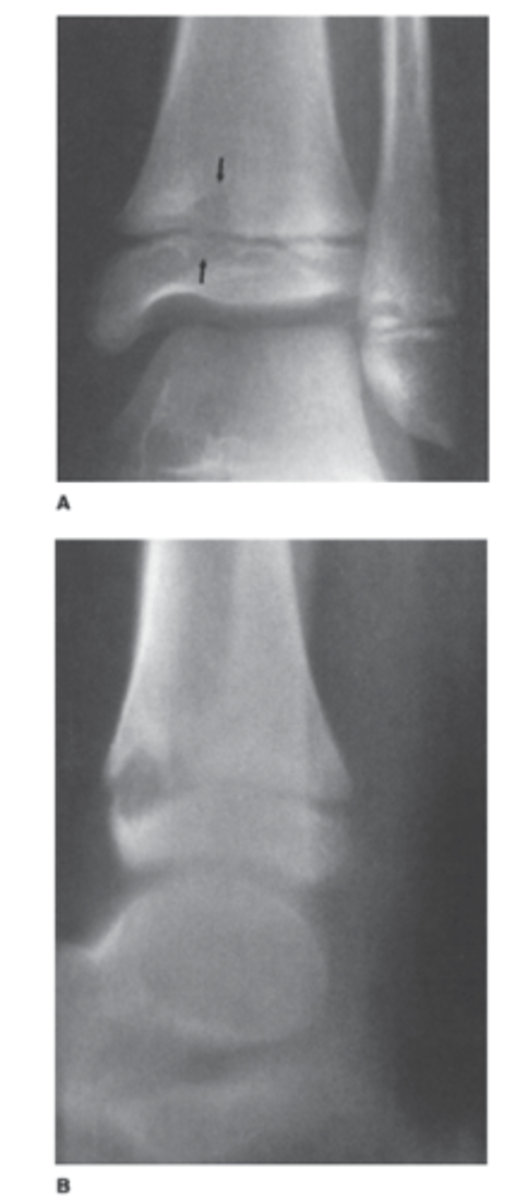

A 15-year-old boy complains of ankle pain after a fall (AP and lateral views of the ankle).

What is the abnormality in Case 6-5 (Figure 6-12)?

A. Sprain of the lateral ligaments

B. Fracture of the distal fibula

C. Stress fracture of the talus

D. Triplane fracture of the distal tibia

Answer

D.

Note how the lucencies rule vertically through the epiphysis and obliquely through the metaphysis. This is also called a Salter Harris IV fracture